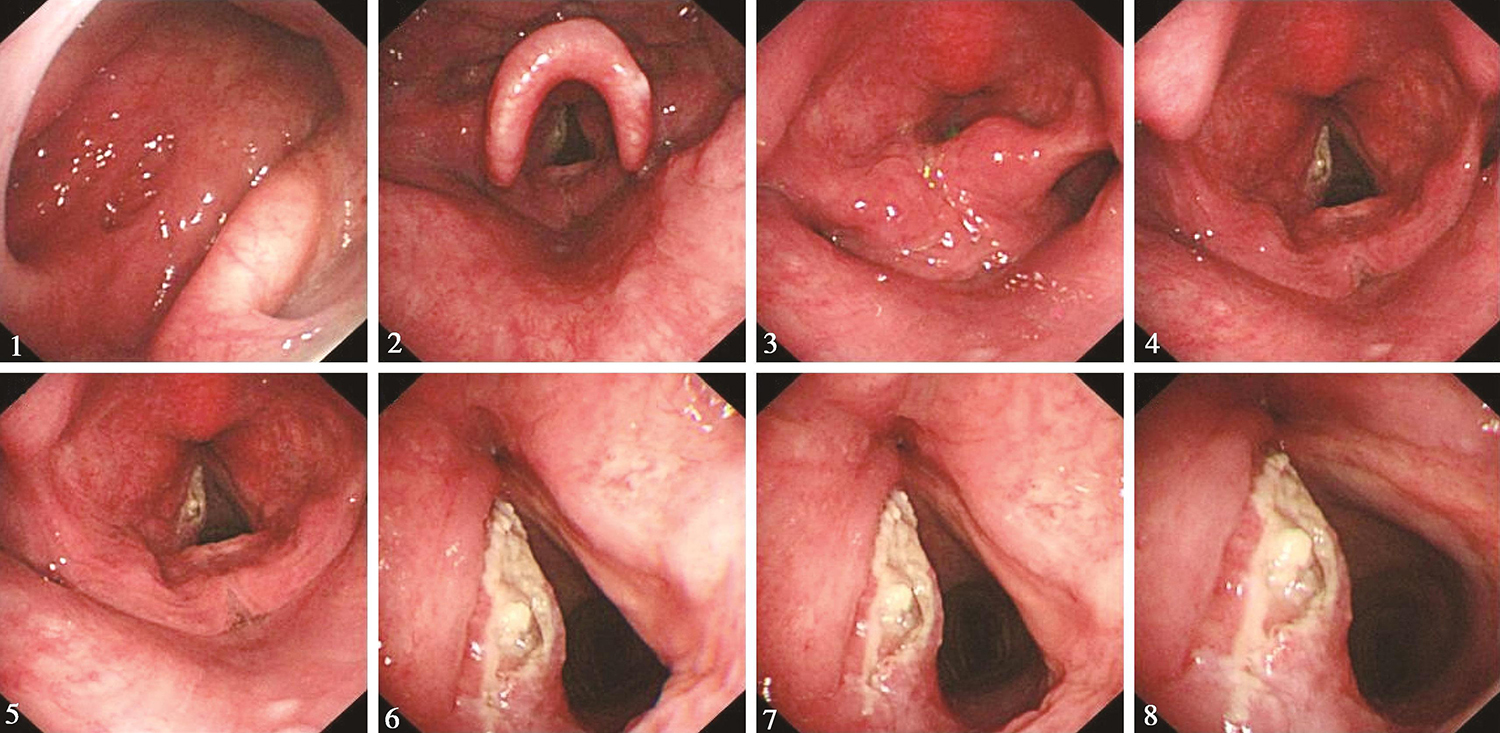

1.2017年2月8日电子鼻咽喉镜检查

鼻腔进镜顺利。鼻咽部结构完整,黏膜光滑,未见明显异常。口咽双侧扁桃体未见肿大。舌根部淋巴滤泡略增生。下咽部表面基本平整,未见明显异常。喉部声门上结构完整,双侧披裂结构基本对称。左侧声带可见肿物生长(活检4块),表面有溃疡,坏死物覆盖,累及全长,向前达前联合,向后达声带突。右侧声带光滑。左侧声带活动受限,右侧声带活动正常(图1)。

图1 喉镜示左侧声带肿物

内镜所见:“喉癌术后半年”鼻腔进镜顺利。鼻咽部结构完整,黏膜光滑,未见明显异常。口咽双侧扁桃体略肿大。舌根部淋巴滤泡略增生。下咽部表面基本平整,未见明显异常。喉部结构完整,双侧披裂结构正常。左侧声带切除,右侧声带光滑。左侧喉部活动明显受限,右侧声带活动正常(图3)。

图3 2017年8月23日复查喉镜示左侧声带切除,右侧声带光滑